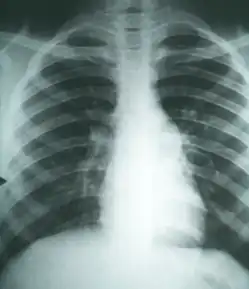

Imaging

Chest X-rays rarely demonstrate nodules or cavities in the lungs, but these images commonly demonstrate lung opacification, pleural effusions, or enlargement of lymph nodes associated with the lungs.[3] Computed tomography scans of the chest are more sensitive than chest X-rays to detect these changes.[3]